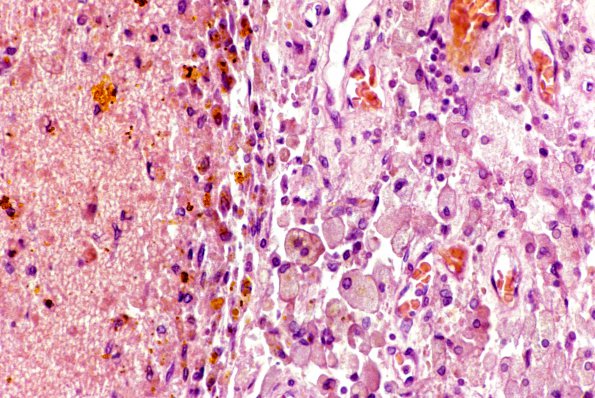

High magnification of the resolving margin of a subdural membrane (H&E)